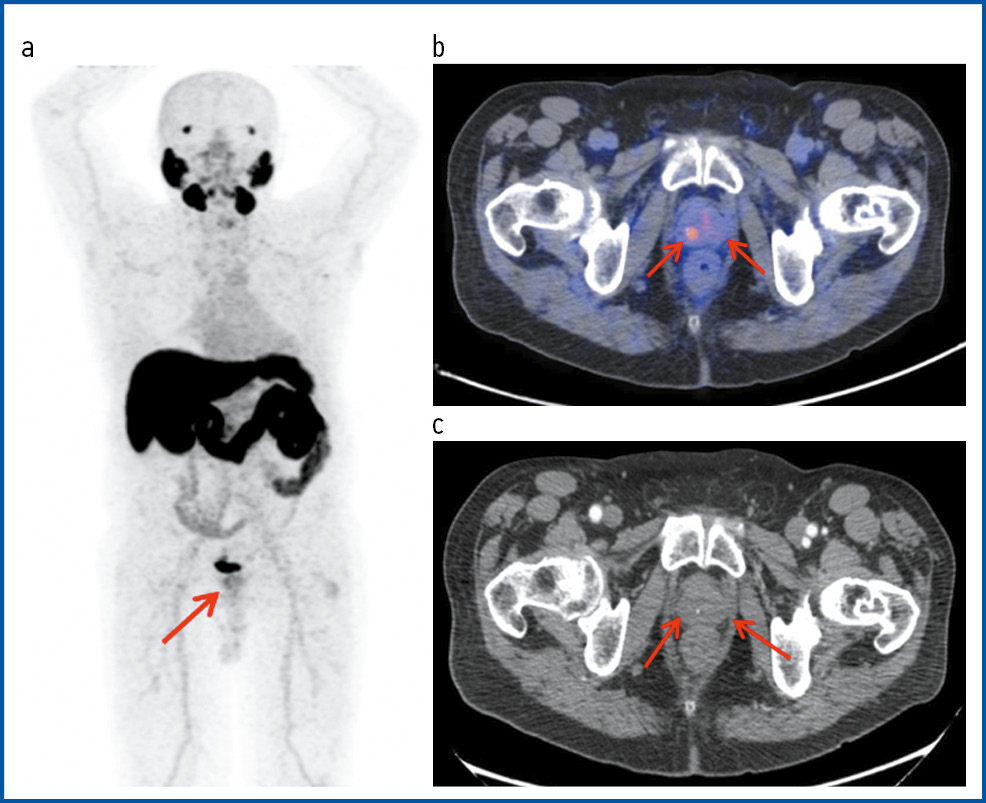

Рис. 4. Пациент А., 72 года. ПЭТ/КТ с 18F-PSMA. РПЖ, стадия pT3bN1M0G2. 3 + 4 = 7 по Глисону. Состояние после радикальной простатэктомии с тазовой лимфаденэктомией. Первично-множественный метахронный светлоклеточный ПКР. Латентный период – 26 мес. На MIP (a), аксиальной проекции КТ (b) и ПЭТ/КТ-исследовании (c) – состояние после радикальной простатэктомии. В области цистуретрального анастомоза справа визуализируется узловое образование с гиперфиксацией РФП, SUVmax 12,36 – рецидив.

Fig. 4. Patient A., 72 years old. PET/CT with 18F-PSMA PCa, pT3bN1M0G2 stage. Gleason score 3 + 4 = 7. State after radical prostatectomy with pelvic lymphadenectomy. Primary multiple metachronous clear cell RCC. The latency period was 26 months. On MIP, the axial view of CT, and pet/CT imaging, the state after radical prostatectomy was visualized. In the area of bladder-urethral anastomosis, a nodule with RPA hyper uptake was visualized on the right, SUVmax 12.36. Findings consistent with relapse.